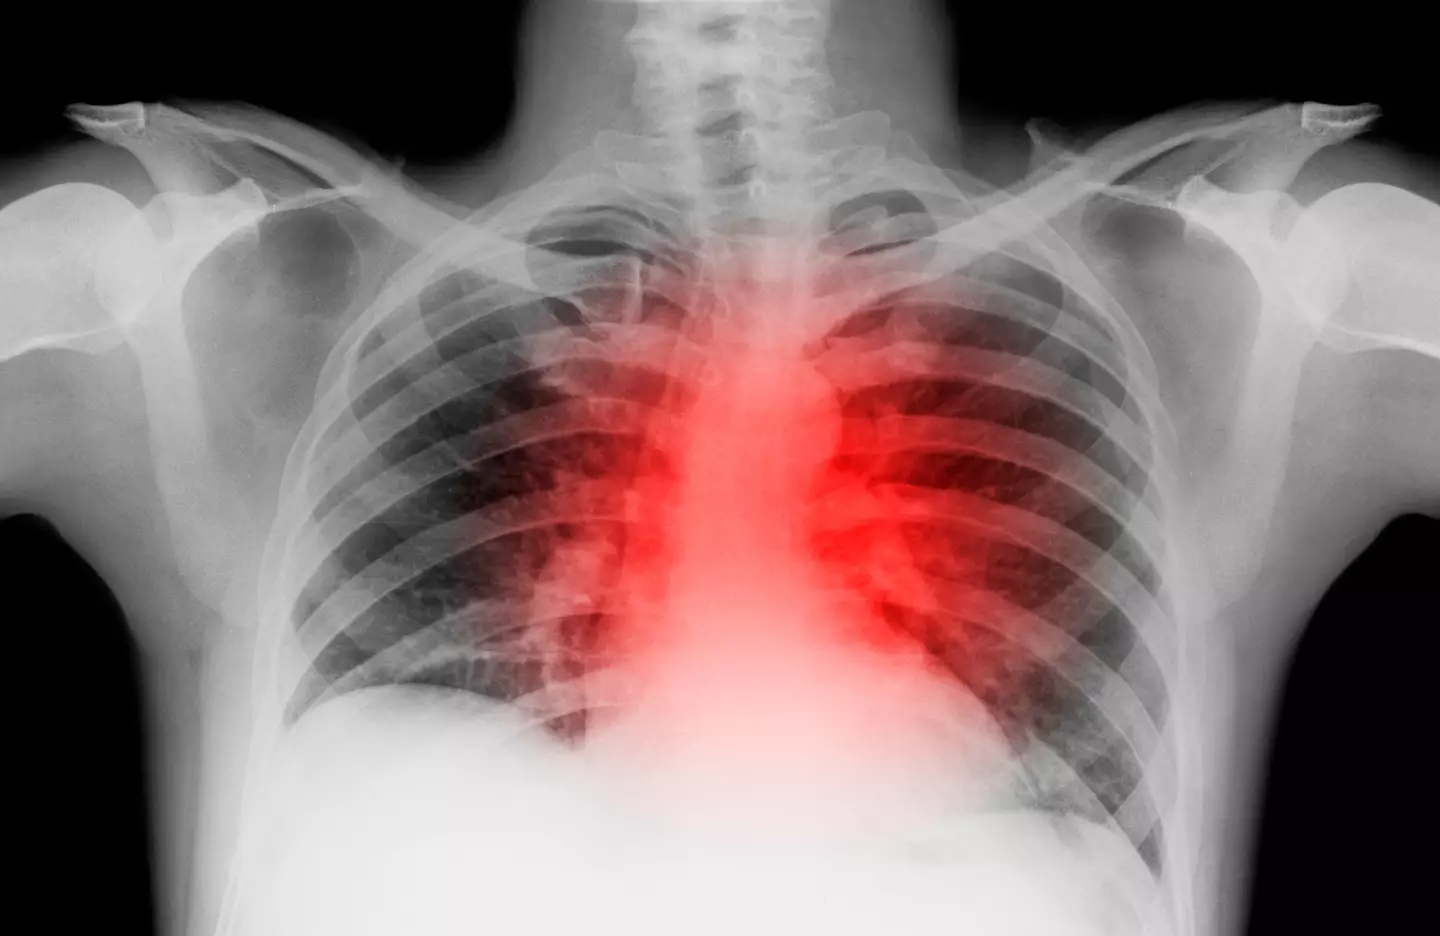

In fact, it can possibly indicate poor cardiovascular health - in other words, issues related to the heart and blood vessels.

However, many studies have noted the presence of the unusual mark in those with cardiovascular issues, such as heart disease and atrial fibrillation, a condition which causes an irregular heartbeat.

Speaking about earlobe creases and the association with cardiovascular health, Tim Chico, Professor of Cardiovascular Medicine at the University of Sheffield said: "Cardiovascular disease isn't just something that affects the heart, it affects all the blood vessels around the body and all organs.

"It increases the risk of heart attacks and stroke but also kidney disease and even dementia.